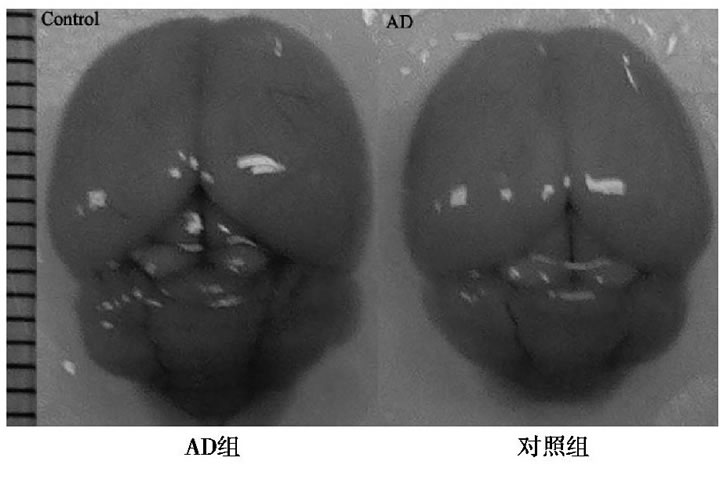

2.1 AD和對(duì)照組全腦圖

與對(duì)照組比較, AD小鼠完整腦組織表面泛白、無血色, 血管明顯減少, 表明D-半乳糖聯(lián)合三氯化鋁已經(jīng)對(duì)小鼠的腦組織形成退行性損傷。見圖1。

圖1 AD組和對(duì)照組小鼠全腦圖